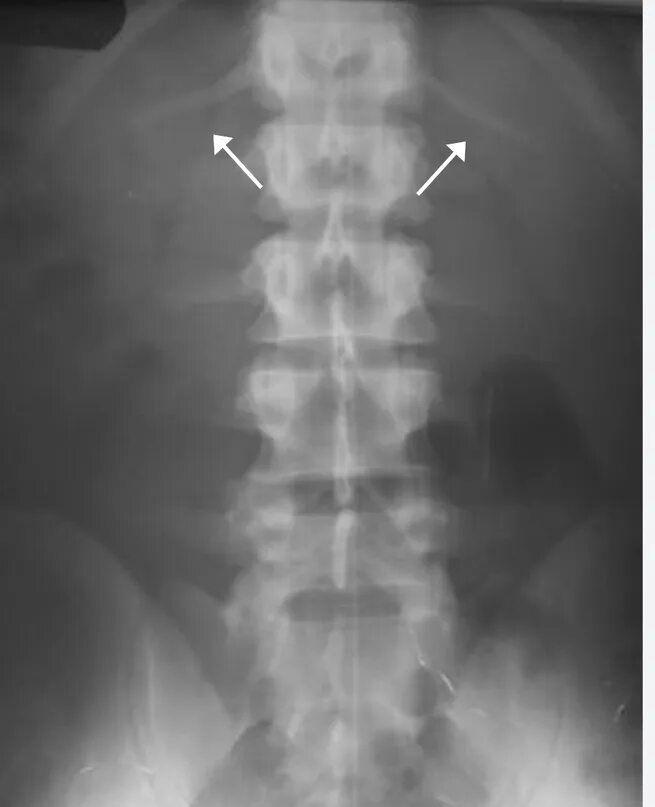

Гипоплазия 12 пары ребер